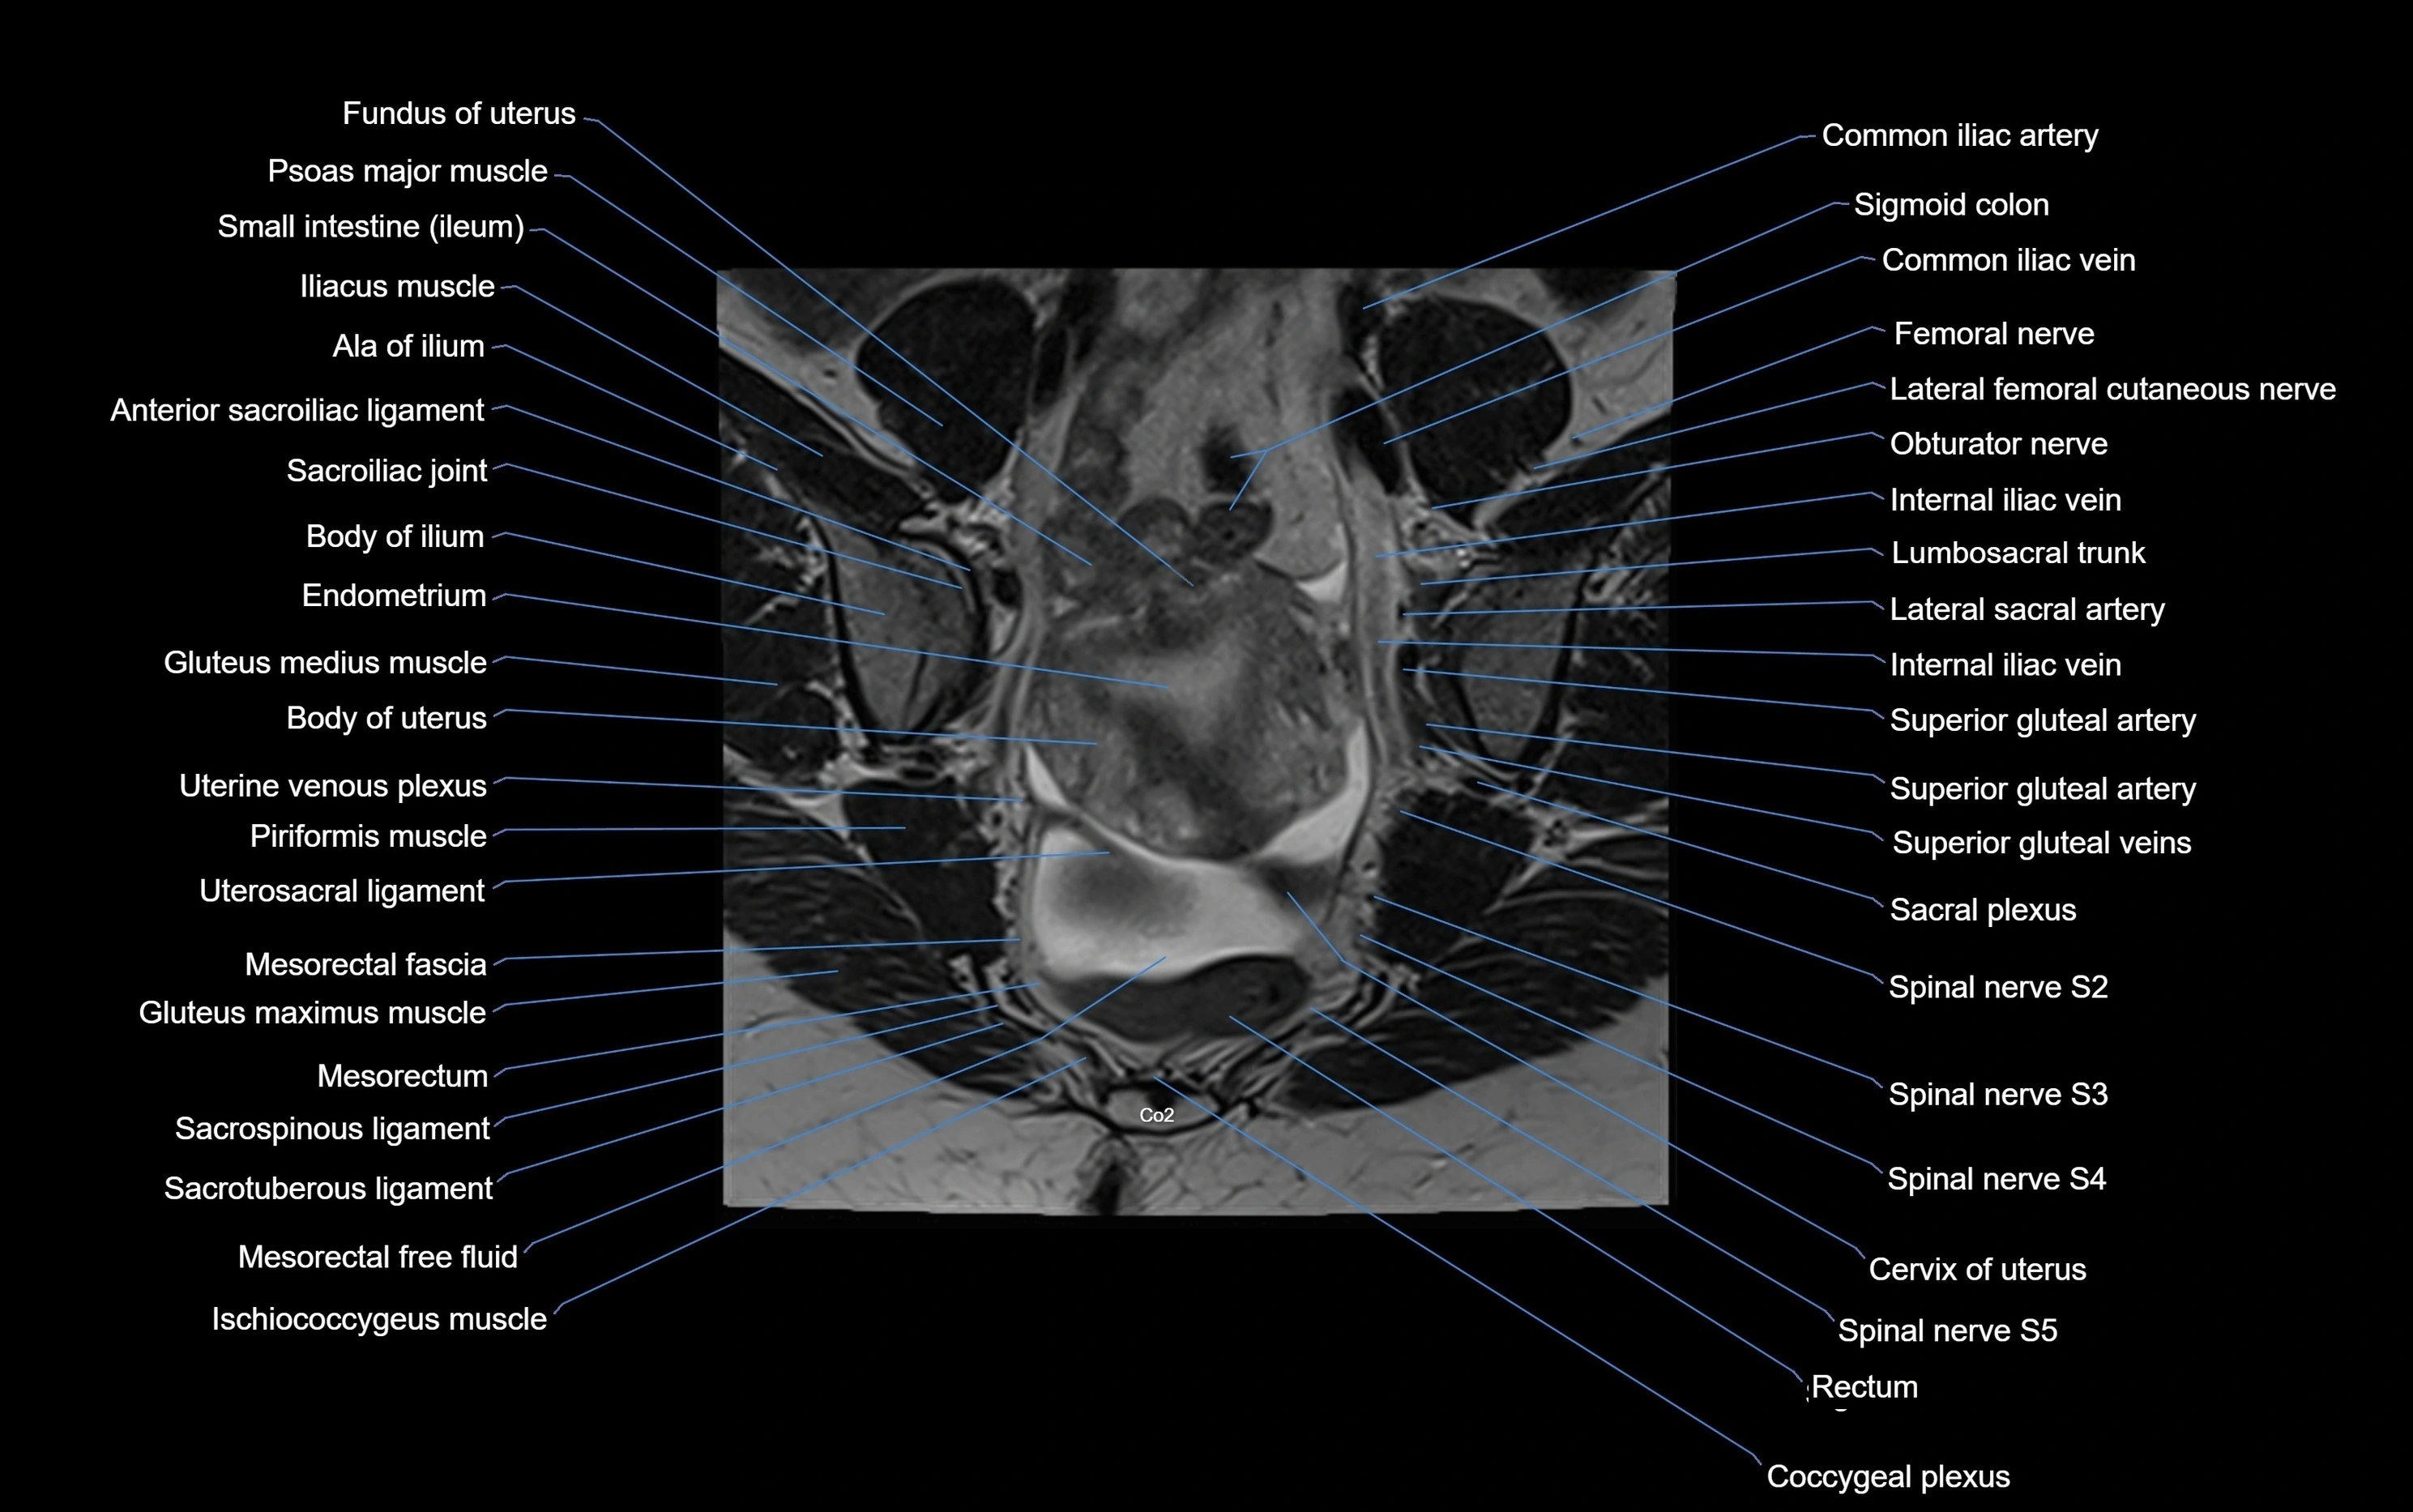

MRI image

image